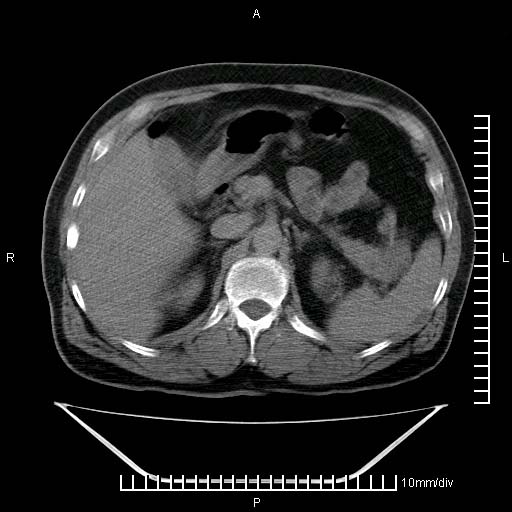

标题: CT25082:肝脏增强:男性,70岁 [打印本页]

标题: CT25082:肝脏增强:男性,70岁

患者以心脏疾病收住院,腹部无明显症状,b超查肝脏有占位。